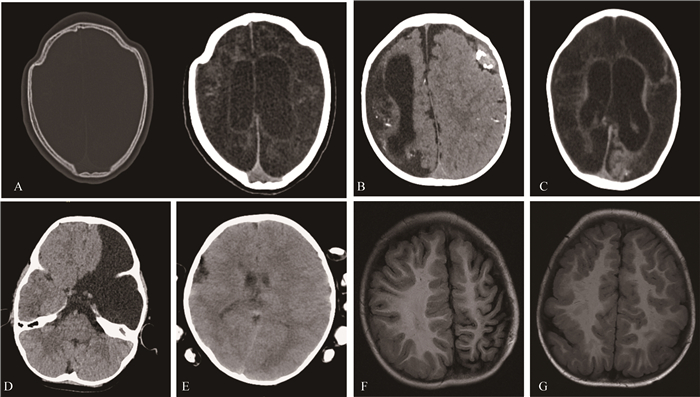

Fig 2 Imaging demonstrations of CNS malformations in the 1- to 3-year-old group and>3-year-old group A: The irregular contour of the cranium suggests craniosynostosis in a 24-month-old infant (left) and the relatively low density in both cerebral parenchyma was found(right); B: The dysplasia of gyrus in the right hemisphere and the corresponding porencephaly was found on CT image in a 24-month-old infant. The high-density hematoma was also found in the contralateral subdural space; C: The CT indicated the extent low density of both cerebral parenchyma in a 36-month-old infant. D: The absence of left frontal lobe in axial CT was found in a 48-month-old child. The subsequent follow-up demonstrated the barylalia with normal movement function; E: The giant gyrus in the right and the polygyria in left hemisphere on CT was found in a 60-month-old child. F: The dysplasia of left both frontal and parietal lobe was found on MRI in a 48-month-old infant. G: The polygyria was found in both the bilateral frontal and parietal lobe on axial MRI in a 48-month-old infant.